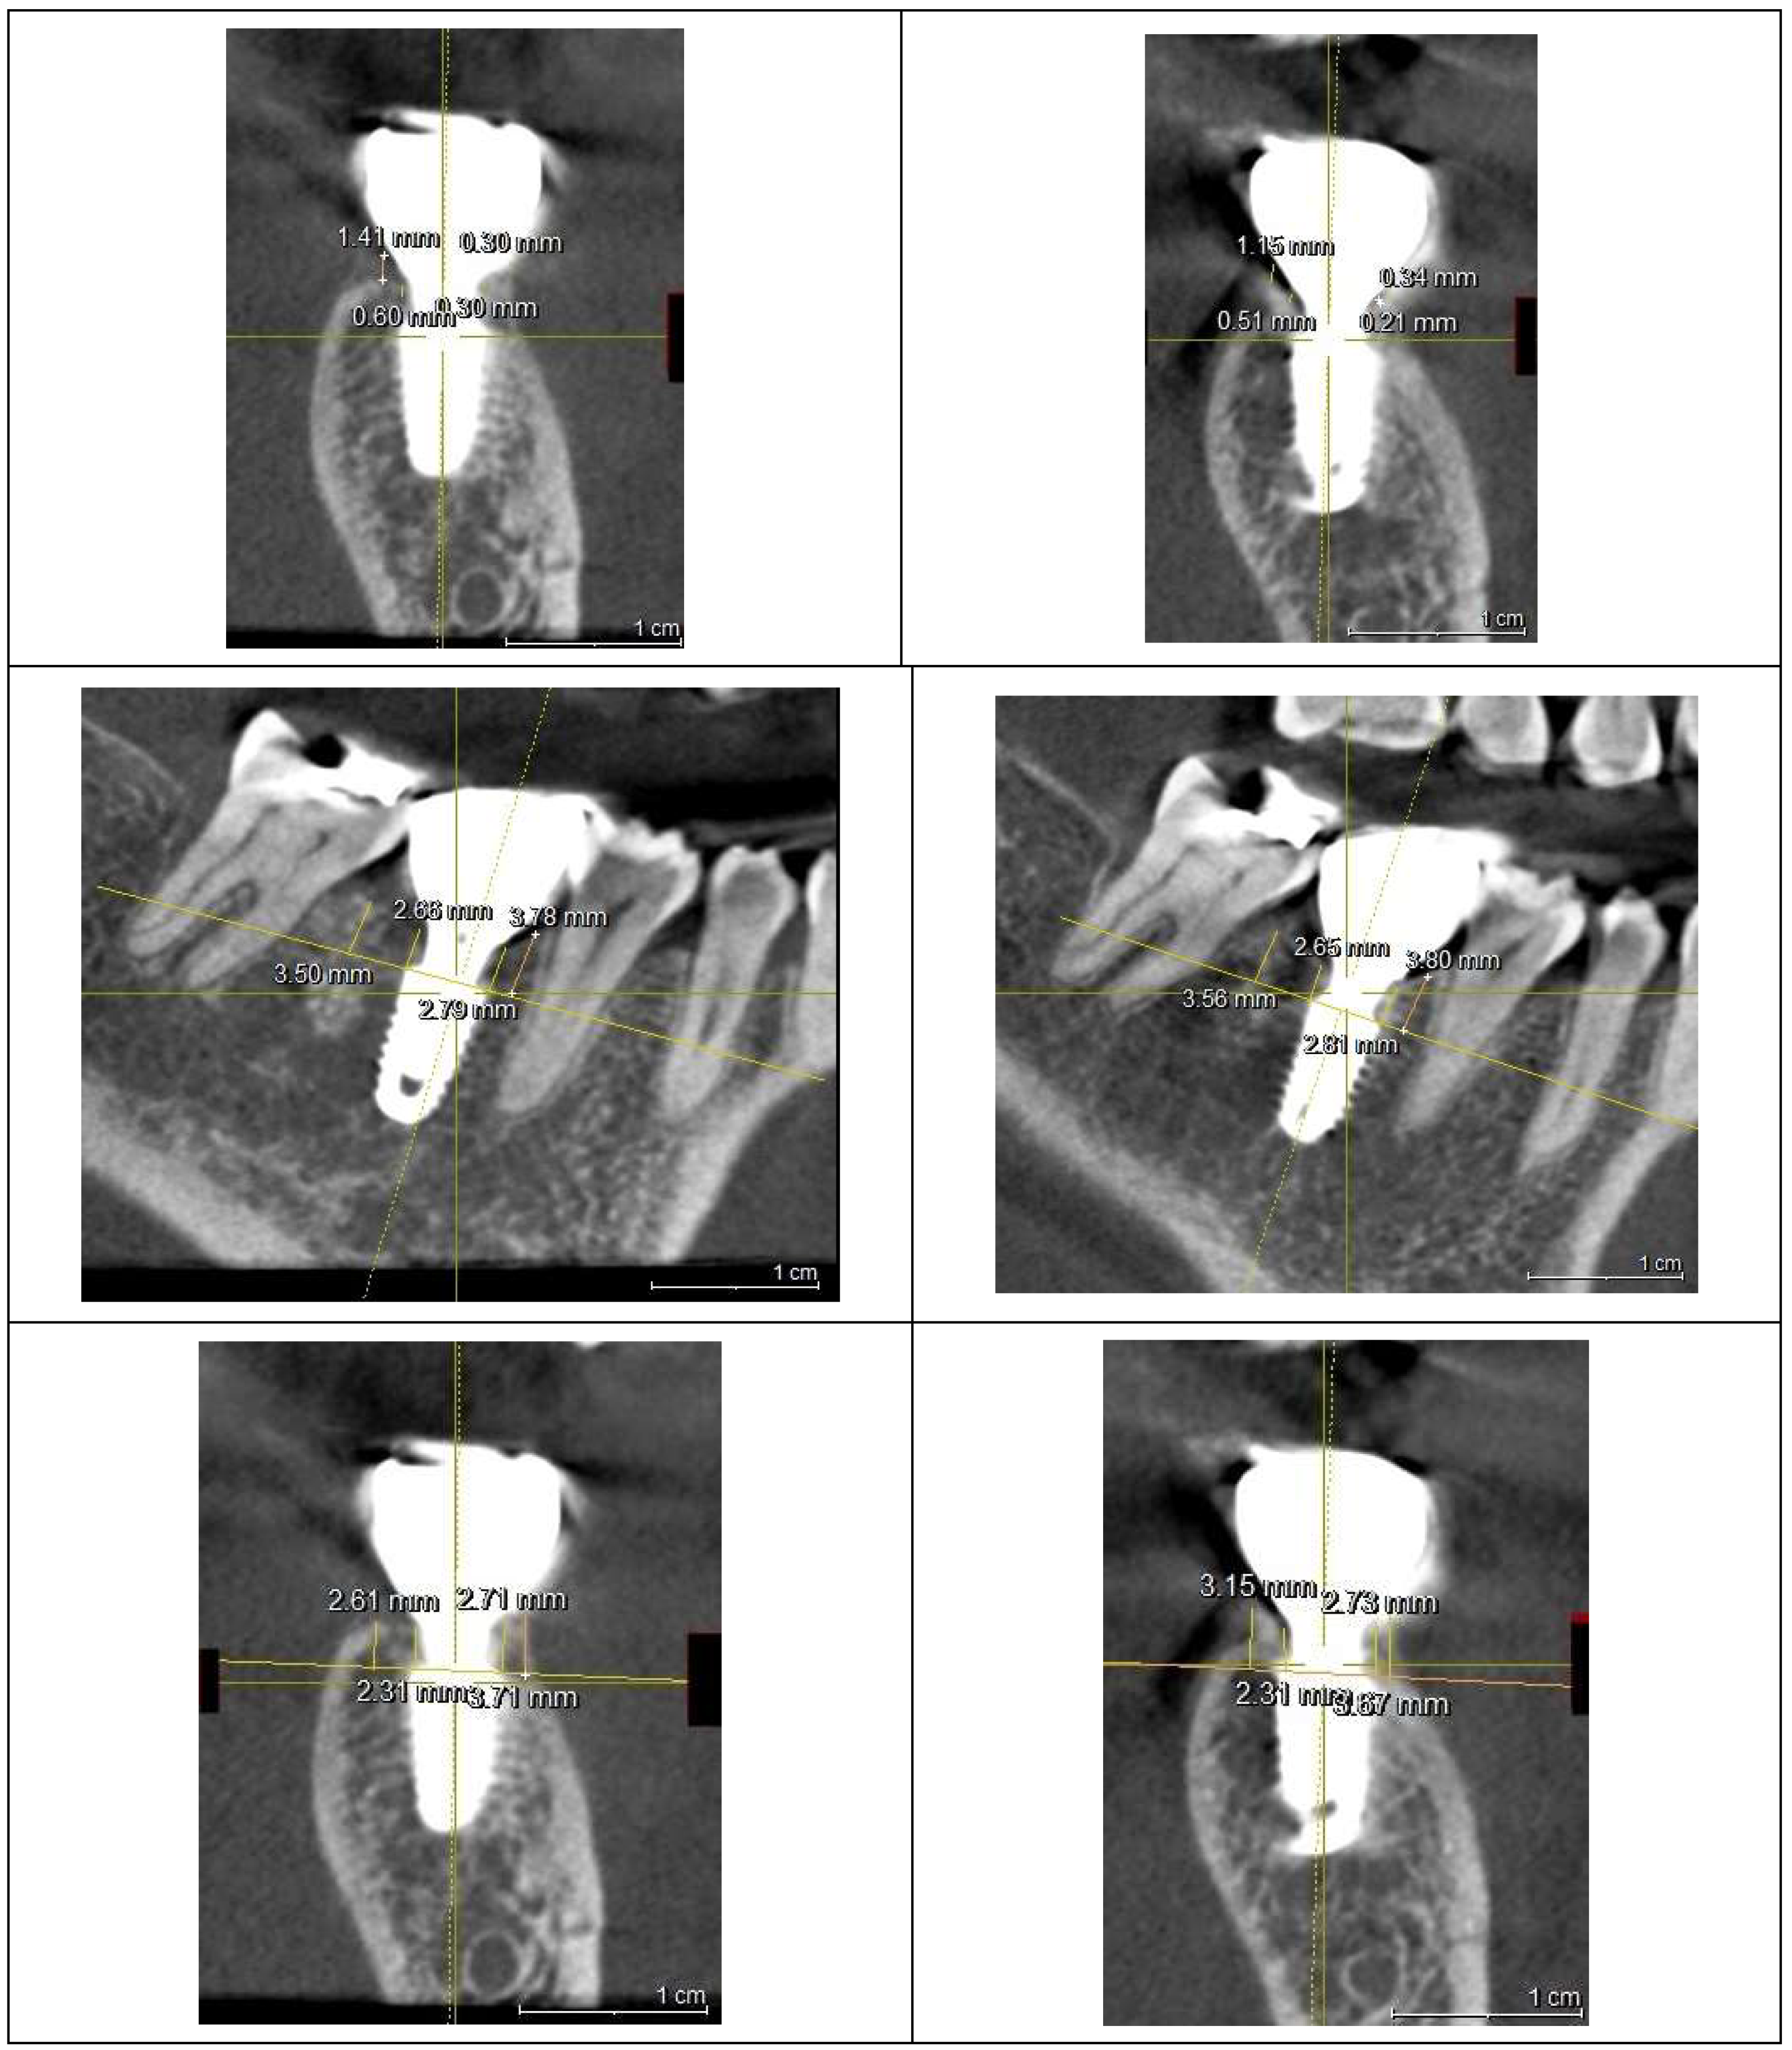

To assess peri-implant soft tissue structure and bone topography, a Cone-Beam Computed Tomography (CBCT) scan was performed, focusing on the Crest to Restoration Distance (CRD)—the vertical distance between the implant restoration and the crestal bone—to identify the optimal treatment approach. The results are summarized in

Table 1.

presents the measurements of the Crest to Restoration Distance (CRD), which quantifies the vertical distance between the implant restoration and the crestal bone. The values are divided into central CRD (cCRD) and peripheral CRD (pCRD) to distinguish the dimensional variations along the implant interface. These measurements are taken at both central and peripheral locations, evaluating the mesial (M), distal (D), buccal (B), and lingual (L) aspects around the implants of the upper left first molar and lower first molar. The data were collected from the CBCT scan conducted on October 26, 2021.

CRD refers to the vertical space between the crestal bone and the implant restoration. It is measured at two locations: centrally (cCRD) and peripherally (pCRD) to evaluate dimensional variations along the implant interface.

The CRD for the upper left first molar implant was consistently larger than that for the lower right first molar implant. The central CRD (cCRD) difference was 0.97 mm (1.48 mm – 0.51 mm), while the peripheral CRD (pCRD) difference was 0.90 mm (1.97 mm – 1.07 mm). As no CBCT-based CRD measurements exist in the literature, a clinical study by Won, analyzing CRD (or Soft Tissue Thickness, STT) in 20 cases of subcrestally placed implants with stable outcomes over two years, served as a reference. That study reported an average pCRD of 0.6 mm and cCRD of 0.3 mm (

The two implant sites were analyzed in a split-mouth study using CBCT scans from 2021 and 2024 to assess peri-implant soft tissue and bone structure. CRD and DP measurements were obtained through CBCT imaging and clinical evaluations to examine their correlation with peri-implant health, particularly in managing peri-implant mucositis.

Panoramic and CBCT scans were taken using Sirona Dental Systems (ORTHOPHOS XG 3D or AXEOS) and analyzed with SIDEXIS and GALILEOS Implant Viewer (version 1.9.5605.25519 ID7).

Radiographic Measurements

Crest to Restoration Distance (CRD)

CRD was measured at two locations:

Central CRD (cCRD): The vertical distance from the crestal bone to the restoration at the outer edge of the implant fixture diameter.

Peripheral CRD (pCRD): The vertical distance at the most peripheral part of the crestal bone in the buccolingual direction and at the most coronal midpoint of the mesiodistal crestal bone.

Figure 7 and

Figure 8 illustrate the radiographic changes observed from 2021 to 2024 at the lower right first molar implant site (control site) and the upper left first molar implant site (experimental site), respectively. (

Figure 7.

This image illustrates the X-ray measurements conducted on the lower right first molar implant, comparing data from 2021 and 2024.

Figure 8.

This image illustrates the X-ray measurements conducted on the upper left first molar implant, comparing data from 2021 and 2024.